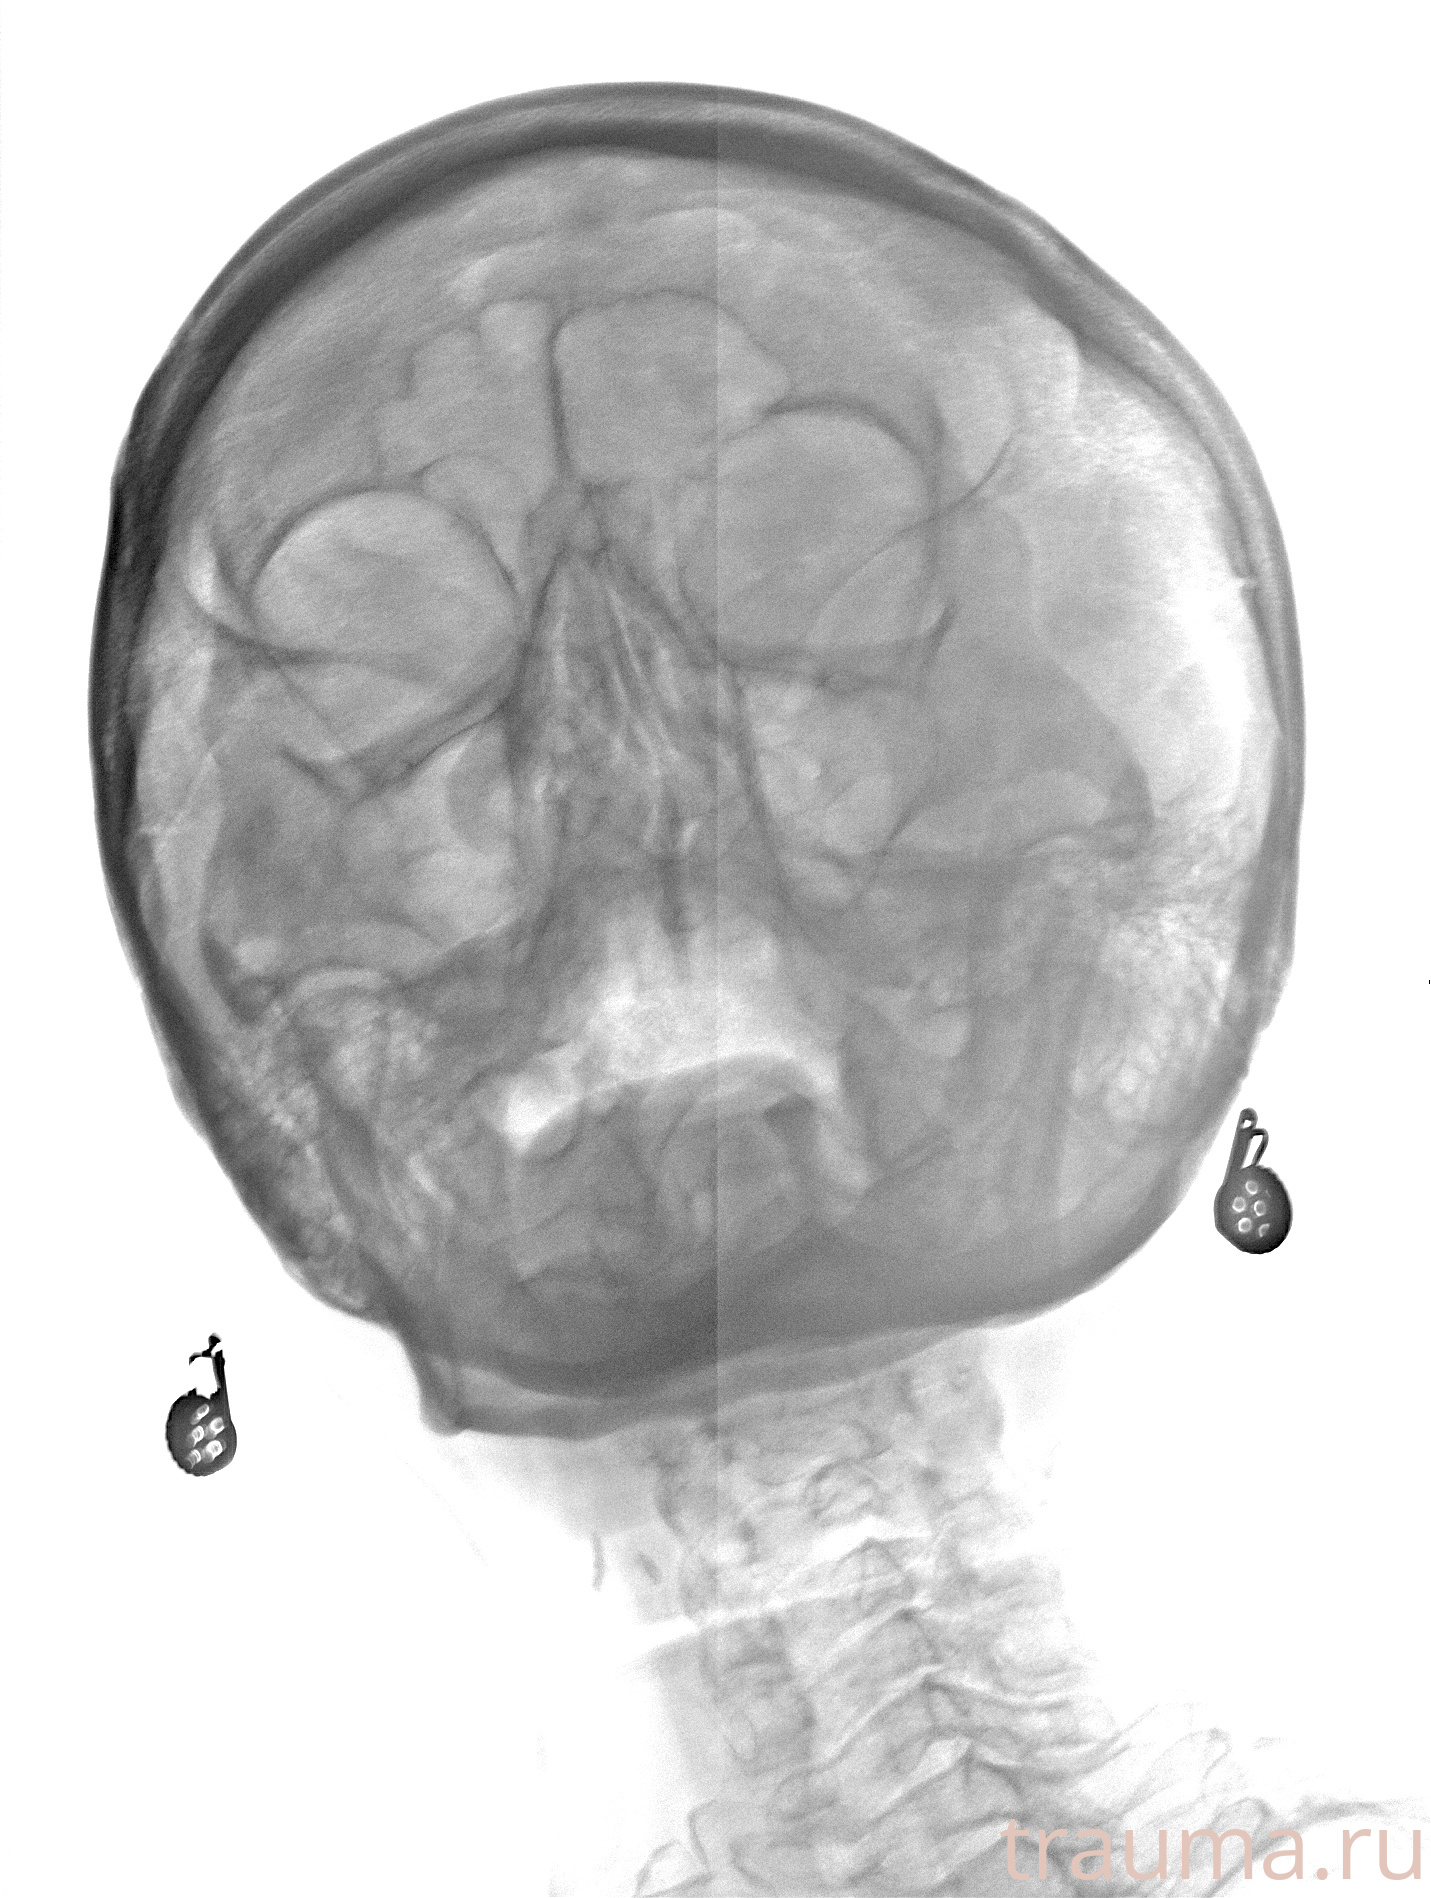

Рентгенограммы

Рентген на дому: по вашему адресу приезжает врач-рентгенолог, травматолог-ортопед с мобильным рентгеновским аппаратом, проводит диагностику травмы или заболевания, делает необходимые рентгенограммы, дает рекомендации по дальнейшему лечению. Получить качественные снимки в домашних условиях возможно благодаря уникальной методике, разработанной МосРентген Центром для института  Склифосовского